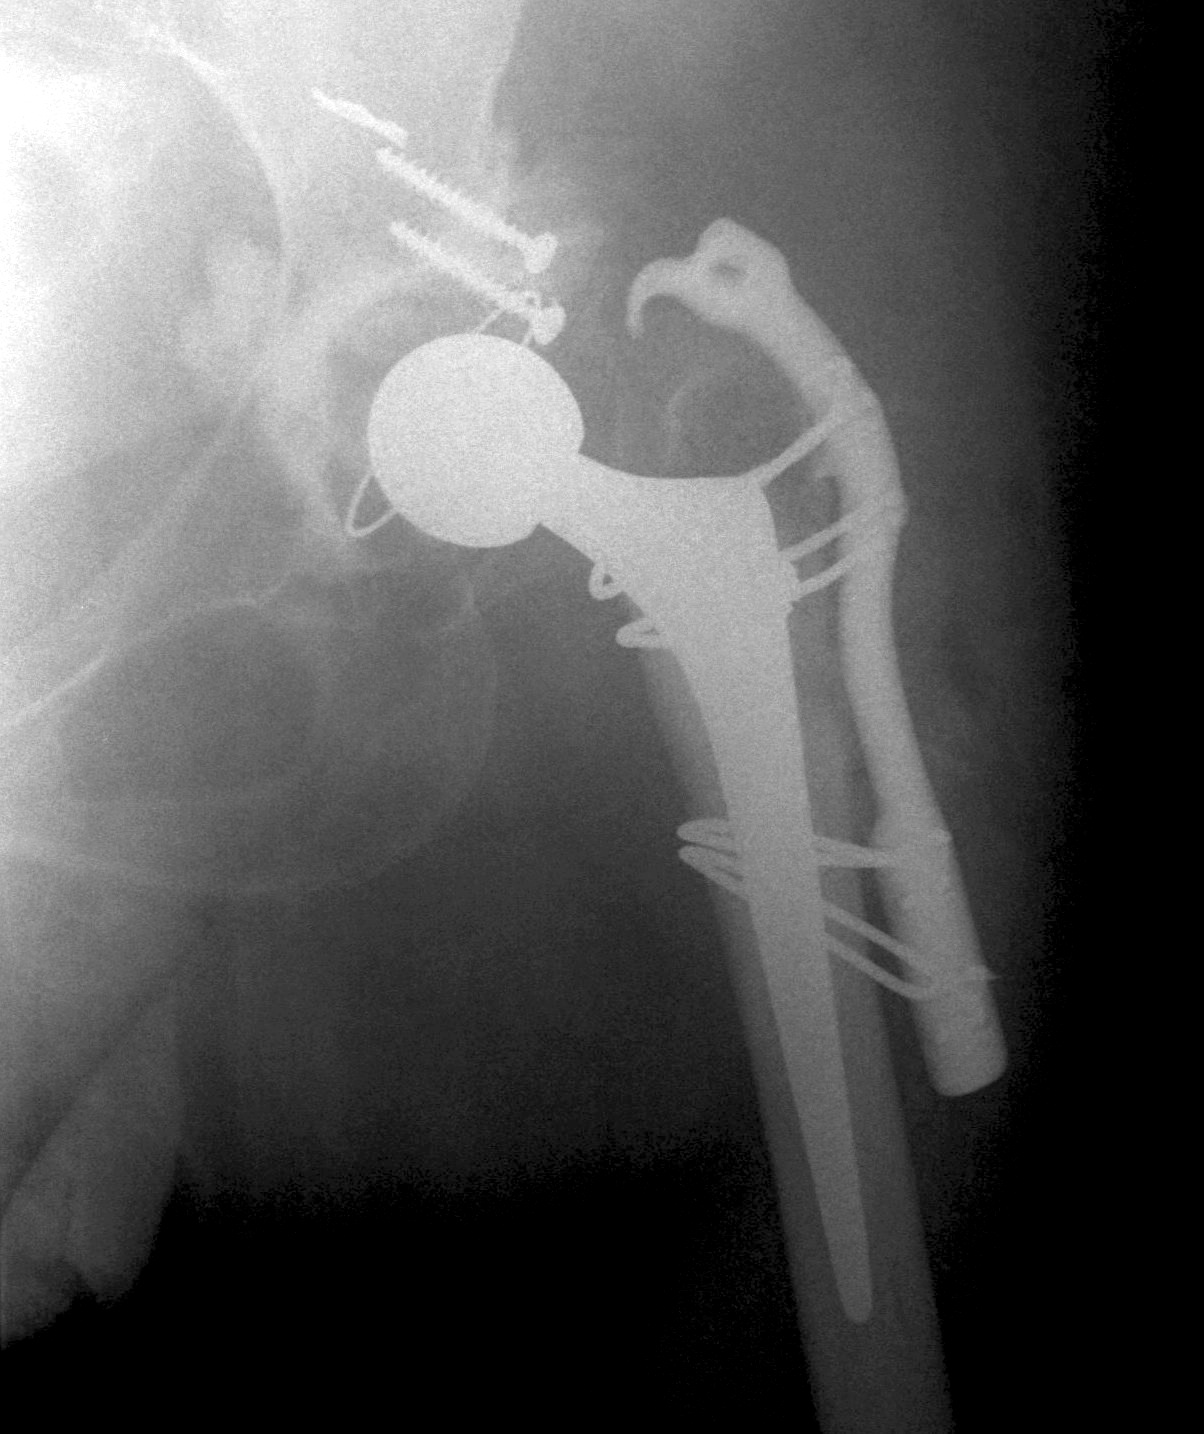

Femoral shortening / Subtrochanteric osteotomy

Technique

Vumedi subtrochanteric osteotomy for Crowe IV

Options

- transverse / oblique / chevron / step cuts

Li et al BMC Musculoskeletal 2014

- systematic review of trochanteric osteotomy for DDH THA

- 37 studies and 800 hips

- no difference in outcomes (nonunion, revision) for transverse versus stepcut

Wang et al J Arthroplasty 2017

- 76 Crowe IV THA

- transverse osteotomy with uncemented stem

- 1/76 nonunion

- 1 acetabulum and 1 femoral stem revised at mean 10 years